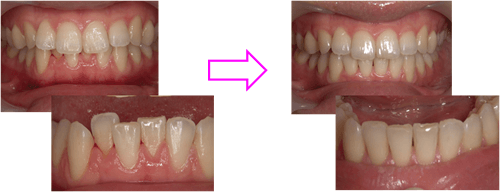

症例.1 モダン矯正

| 術前 | 術後 |

|---|---|